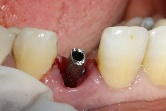

The surgical guide was placed and fixed (Figure 7) and we began the drilling sequence, to place a biotech 3,6/12 implant (Figure 8).

Figure 7. Placement of the surgical guide

Figure 8. Drilling sequence

After implant placement (Figure 9), the primary stability of the implant was satisfactory (greater than 35N), the provisional abutment was fixed (Figure 10) and a post-operative retroalveolar radiograph was taken for radiological control of the implant and adaptation of the provisional abutment (Figure 11).